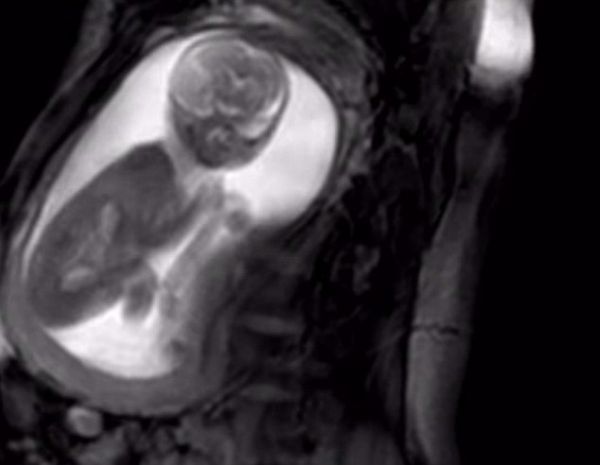

• 医健资讯|核磁共振成像扫描技术推出,观察胎儿活动更清晰 9年前

据英国《每日邮报》网站2月8日报道,英国伦敦国王学院、圣托马斯医院、帝国理工学院、佛罗伦萨大学、多伦多儿童医院和飞利浦医...